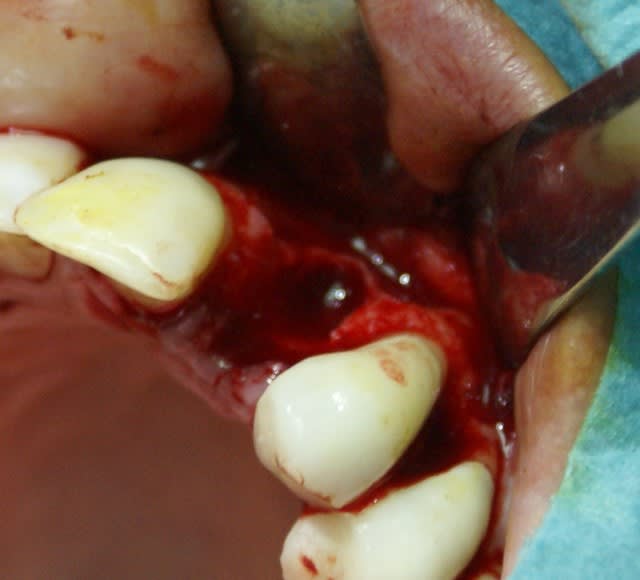

Tout à fait d'accord growler et c'est d'ailleurs ce que l'on peut voir sur le cas suivant. Fracture radiculaire, aucune infection periradicualire. Extraction et implantation immediate. Espace existant entre l'implant et l'alvéole est comblé par du BioOss. Un logement sous gingival est formé en vestibulaire et palatin de facon à pouvoir recouvrir le tout par BioGide et un conjonctif enfoui.

L'implant est de 15mm mais l'alvéole était large et 50% environ de la surface implantaire n'était en contact qu'avec du BioOss. J'ai pour cela préféré enfouir.